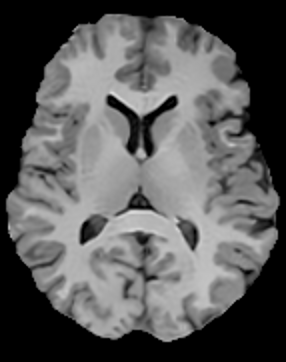

In this subsection, the MRI images from the built-in MRI dataset available in the MATLAB® toolbox have been used as test subjects. Specifically, the denosing algorithms have been tested using the axial slices number 4, 7 and 16 (shown in Figures 5, 5 and 5, respectively), which represent a spectrum of different cerebral structures. For quantitative comparison, simulated data have been obtained by subjecting the original test images to various levels of Rician noise.

Figure 5: (a) Test slice #4, (b) Test slice #7 and (c) Test slice #16 of the MATLAB® MRI database.